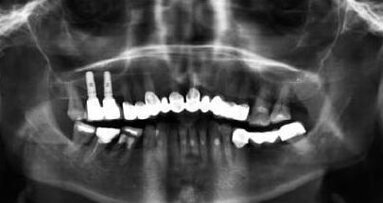

Odbudowy implantoprotetyczne w bocznym odcinku szczęki niejednokrotnie wymagają dodatkowych zabiegów z zakresu sterowanej regeneracji kości, w celu zapewnienia odpowiedniej ilości tkanki kostnej, potrzebnej do pogrążenia implantu w prawidłowej pozycji.1 W wyniku utraty zęba przedtrzonowego lub trzonowego górnego dochodzi do pneumatyzacji zatoki szczękowej, zmniejszającej wymiar wertykalny kości.2 W takim przypadku wykonuje się zabieg podniesienia dna zatoki szczękowej, co można wykonać przy pomocy kilku podstawowych technik oraz ich licznych modyfikacji.3

W 2015 r. polski autor Radosław Jadach przedstawił pracę oryginalną, w której opisuje zabieg podniesienia dna zatoki szczękowej z dostępu od strony podniebiennej jako metody alternatywnej.7 Zabieg wykonano u 39 pacjentów. Autor opisuje również własną klasyfikację, na podstawie której łatwiejsze będzie podjęcie decyzji odnośnie tego która z metod podniesienia dna zatoki szczękowej będzie bardziej odpowiednia dla danego przypadku klinicznego. Klasyfikację tę autor stworzył na podstawie analizy 200 badań tomografii komputerowej wiązką stożkową (CBCT). Klasyfikacja przedstawia podział ze względu na grubość blaszki kostnej od strony przedsionkowej i podniebiennej w sposób następujący:

Daisuke i wsp. opisali przypadek, gdzie zastosowanie dostępu od strony podniebienia było uzasadnione i stanowiło jedyną możliwość, aby pacjent mógł w przyszłości mieć wykonaną odbudowę implantoprotetyczną.8 Ze względu na niewystarczający wymiar pionowy kości nie można było pogrążyć implantów w pożądanych pozycjach, zatem zdecydowano się wykonać podniesienie dna zatoki szczękowej z dostępu klasycznego od przedsionka. Podczas zabiegu doszło do perforacji błony Schneidera o długości ok. 10 mm. Perforację zaopatrzono oraz dokończony procedurę augmentacji materiałem kościozastępczym. Po wykonaniu kontrolnego zdjęcia CBCT po upływie 5 miesięcy stwierdzono niewystarczającą formację tkanki kostnej od strony podniebienia oraz w części dystalnej. Ze względu na to, że od strony przedsionka doszło do prawidłowej osteogenezy, zdecydowano o wykonaniu zabiegu augmentacji od strony podniebienia. Następnie wprowadzono 2 implanty podczas tej samej wizyty, co wskazuje na odmienne postępowanie niż zalecane przez Jadacha.